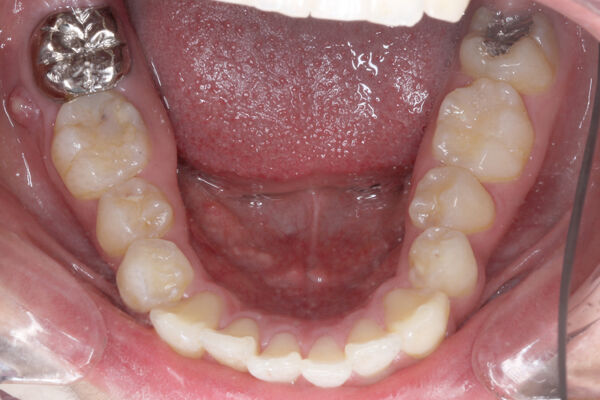

次の患者さんは顎を包むように左側全体に手があたるような頬杖でした。

下の歯は前歯までの広い範囲がへこんでいます。